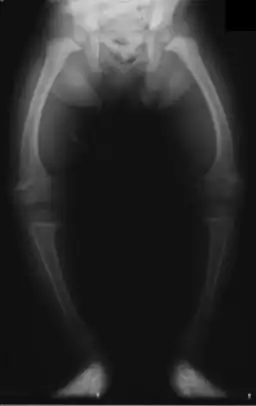

Radiografia de criança de dois anos com raquitismo, com fémures arqueados e diminuição da densidade óssea

Raquitismo é uma doença metabólica caracterizada por deformações dos ossos em crianças.[4][1] Os sintomas mais comuns são pernas arqueadas, atraso no crescimento, dor nos ossos, deformações cranianas e dificuldade em dormir.[1][2] Entre as possíveis complicações estão fraturas ósseas, espasmos musculares, escoliose ou deficiência intelectual.[1][2]